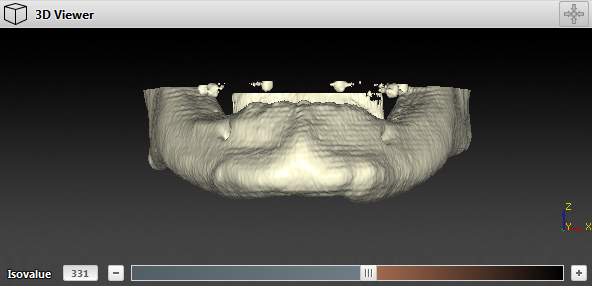

The volume of interest (VOI) or region of interest is that particular part on the 2D view that is selected and considered to be converted into a 3D model. The isovalue defines the boundary of what will be converted into a 3D model.

If the predefined lower threshold does not provide the level of detail desired, you must identify a threshold that is high enough to minimize the noise, but low enough to optimize the bone surface.

When a threshold of 270, for example, seems to be too low because too much noise appears, the threshold must be raised. At 900, the isovalue might seem to be too high because parts of the bone start disappearing and are not covered by the orange mask. A threshold of approximately 400 seems to be correct as there is only a limited amount of noise and all the bone surfaces are colored orange. Therefore, the appropriate threshold must be between 400 and 700.

‒ Drag the isovalue slider to the left or right to define the optimal isovalue.

‒ Enter the value in the isovalue input box.

The 3D surface is defined by all points with a gray value equal to or higher than the indicated isovalue. On the 2D viewer all points that have a gray value equal to or higher than the indicated isovalue are colored orange. This is called a mask. All parts covered by the mask are converted into a surface.